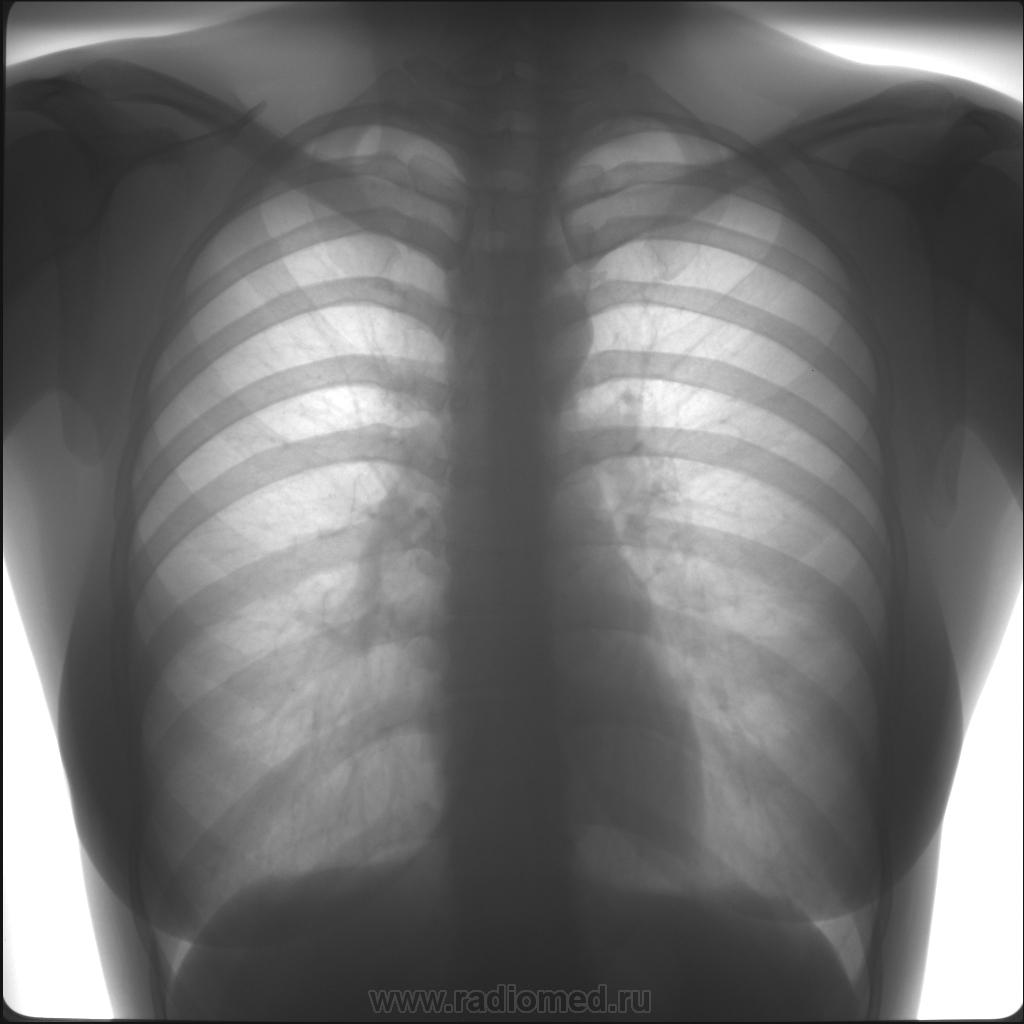

Рентген здоровых легких: примеры снимков и советы

Раздел: Сокровищница опыта